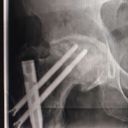

Our dear friend Oliver is facing a major surgery to replace his hip. Anyone who knows Oliver knows just how much he gives to our recovery community — offering support, encouragement, and a listening ear to so many of us on our journeys. Now, it’s our turn to show up for him.

Oliver has already been unable to work since March due to his condition. This has made his financial need even greater, but those who know him also know it’s worth helping him gain the quality of life he deserves — especially after all he has done for others.